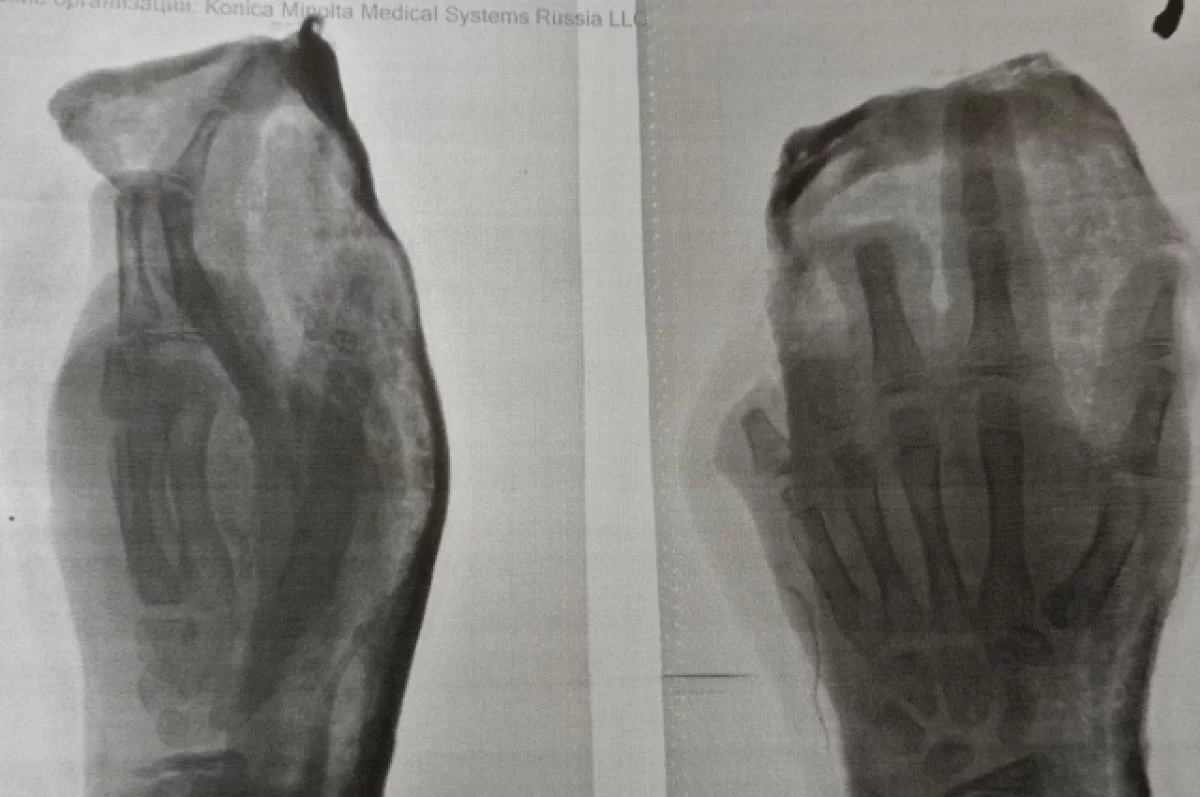

«Одному из пострадавших проведена ампутация III, IV и V пальцев левой кисти. Медики отмечают, что состояние детей тяжёлое стабильное и требует продолжения лечения», — добавили в больнице.

Уточняется, что петарду дети нашли на улице. Когда они попытались поджечь её, изделие взорвалось прямо в руке у одного из них. В результате пострадали оба ребёнка: медики диагностировали повреждения кистей с отрывом пальцев, ссадины лица и травмы глаз.